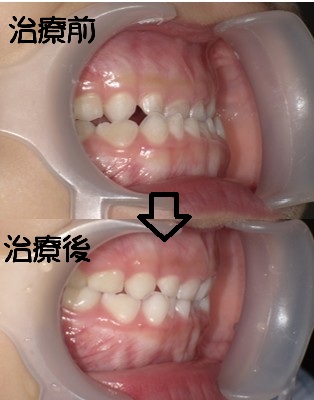

歯が咬み合わない(開咬:奥歯が咬んで前歯が咬み合わない状態)

開咬:奥歯が咬んで前歯が咬み合わない状態口など

・主訴:前歯が噛めないる

・診断:開咬・叢生

・年齢:20歳

・使用した主な装置:マルチブラケット装置

・抜歯部位:第一小臼歯を4本抜去

・治療期間:18か月

・通院回数:24回

・費用の目安:矯正料金として60万+税金。診断料金6.5円+税金。

調整処置料金:月3000円+税金を24回で7万2千円+税金。 第一小臼歯を4本抜去:1本5千円+税金。 総額 832.100円。

リスク・副作用:

・前歯の位置を修正するために、必要上、歯を減らします。

・虫歯にならない様に、通常の歯磨きを工夫することが必要です。

・歯が動く際に、歯のゆれを痛みとして感じることがあります。

・根の吸収が起きることがあります。

・保定をしないと後戻りが起きることがあります。